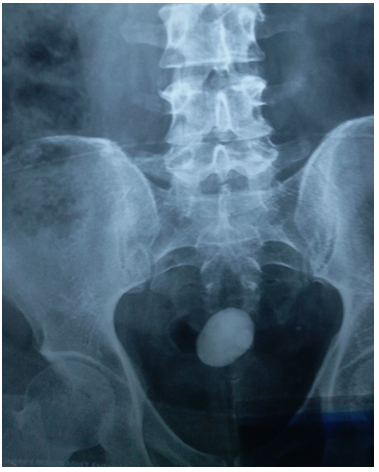

45 years old male patient came to urology outpatient complaining of recurrent right flank pain for several months, no fever or hematuria, no significant medical or surgical history. Physical examination was unremarkable, serum creatinin 1.1mg/dl , urine analysis showed microscopic hematuria, urine culture was negative, ultrasound reveals multiple right renal stones with dilated extrarenal pelvis, plain x ray & intravenous pyelography performed Figure1 (A & B). All treatment options explained to the patient and after discussion he elected to undergo laparoscopic peylolithotomy. Transperitoneal laparoscopic pyelolithotomy was performed in lateral position with Rt. Flank tilted 45 degrees using 4 ports. multiple renal pelvis and calyceal stones extracted and putted in a bag made of No 6 surgical glove (Figure 2) after closure of the pyelotomy by intracorporeal sutures the bag containing the stones extracted through the umbilical port after enlarging it (Figure 2), during extraction the bag was broken and some stones escaped to the abdomen. Another bag replaced and most of the stones extracted searching for the remaining stones in the abdomen was frustrating and we decided to terminate the procedure and closing the port sites. The post-operative course is unremarkable and patient discharged in fifth post-operative day. Follow up plain x-ray after one month revealed tow round stones with 30 and 10mm maximum diameter lying deep in the pelvis (Figure 3), after discussion with the patient about the possible complications of those stones he agree to underwent open extraction by low midline incision and stones extracted.

Figure 1 Pre operative Pain abdominal x ray (A) and intravenous pyelography (B).